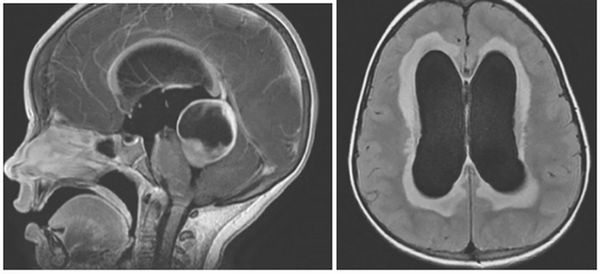

Внутренняя тривентрикулярная окклюзионная гидроцефалия на МРТ во фронтальной и сагиттальной плоскостях: на левом снимке видно гигантское кистозно-солидное образование, явившееся причиной обструкции ликворопроводящих путей на уровне Сильвиева водопровода

Водянка головного мозга при МР-сканировании в коронарной проекции

Проявления патологии на снимках бывают прямыми и косвенными. Первые связаны с расширением желудочков мозга (III, IV и боковых (в начальном периоде — в области передних рогов и тела)), водопровода и/или субарахноидального пространства (конвекситально, в области базальных цистерн, Сильвиевых борозд и пр.). Косвенные признаки на МР-сканах:

- межжелудочковый индекс свыше 0,5;

- перивентрикулярный отек при напряженной водянке;

- смещение гипоталамуса вниз;

- локальное выпячивание крыши боковых желудочков и др.